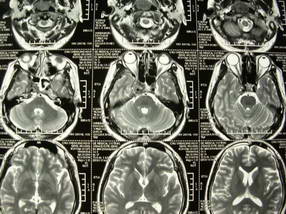

男、30、发现鼻咽部肿瘤侵犯海绵窦,未发现明显淋巴肿。请问国内那家医院治疗鼻咽部肿瘤最好?手术以何种方式为主?病灶可否全部切除?急切期待的大家的帮助。

扫描示鼻咽腔不对称,中度狭窄,右侧咽隐窝消失,局部软组织肿块,鼻咽右侧壁增厚形成肿块,突入鼻咽腔,肿块平扫呈等密度,肿块向深部侵润,右侧翼内外肌受侵,右侧咽旁间隙变窄;向后生长,头长肌界线欠清,向后上生长侵犯同侧颈动脉鞘区。双侧海绵窦增宽,内见软组织影与鼻咽部肿块相连。考虑鼻咽癌。鼻咽癌主要是放射治疗,且效果较好;到当地有治疗设备较大医院治疗即可。